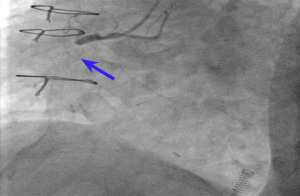

However, he presented as an emergency the next day with the same presentation. Investigations showed a troponin of 189 ng/L (normal <14 ng/L), no dynamic ECG changes, and he was treated for non-ST-elevation MI (NSTEMI) with a high suspicion of stent thrombosis, despite taking all his prescribed medications (No. 4, Table 1). The patient confirmed strict medication compliance. Coronary angiography revealed occlusion of the OM branch stent, a patent RCA stent, and good distal flow (No. 5, Table 1). The decision was made to proceed with PCI to the OM, which revealed fresh thrombus in the stent. Intravascular ultrasound (IVUS) showed an area of under-expanded stent proximally but overall good flow. Unfortunately, he again developed chest pain 2 days after the procedure, with troponin levels rising to 2,000 and 1,700 ng/L (normal <14 ng/L). He underwent emergency percutaneous transluminal coronary angioplasty. Surprisingly, the left circumflex was occluded at the OM stent which operator commented about stent underdeployment which might contribute to stent thrombosis on top of patient’s existing APS. There was also occlusion of the RCA stent (Figure 2). PCI was again performed on the OM and RCA. The patient’s blood pressure dropped during the procedure, and bedside echocardiography showed an ejection fraction of only 20%. He was prescribed a tirofiban infusion for 48 hours after the procedure.

After the procedure, intermittent anginal chest and back pain continued, and repeat angiography showed proximal occlusion of the RCA and OM stent occlusion (Figure 3) (No. 6, Table 1).